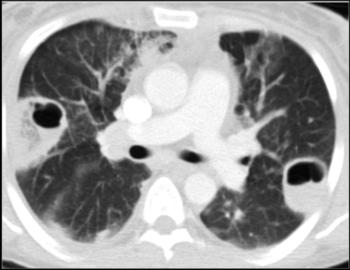

Figure 4. 37-year-old woman presenting with fever, pleuritic chest pain and hemoptysis for 8 days. She referred two heroin injection episodes in the past month. Chest CT image shows peripheral cavitations in both lungs consistent with pulmonary septic emboli.

High-res (TIF) version